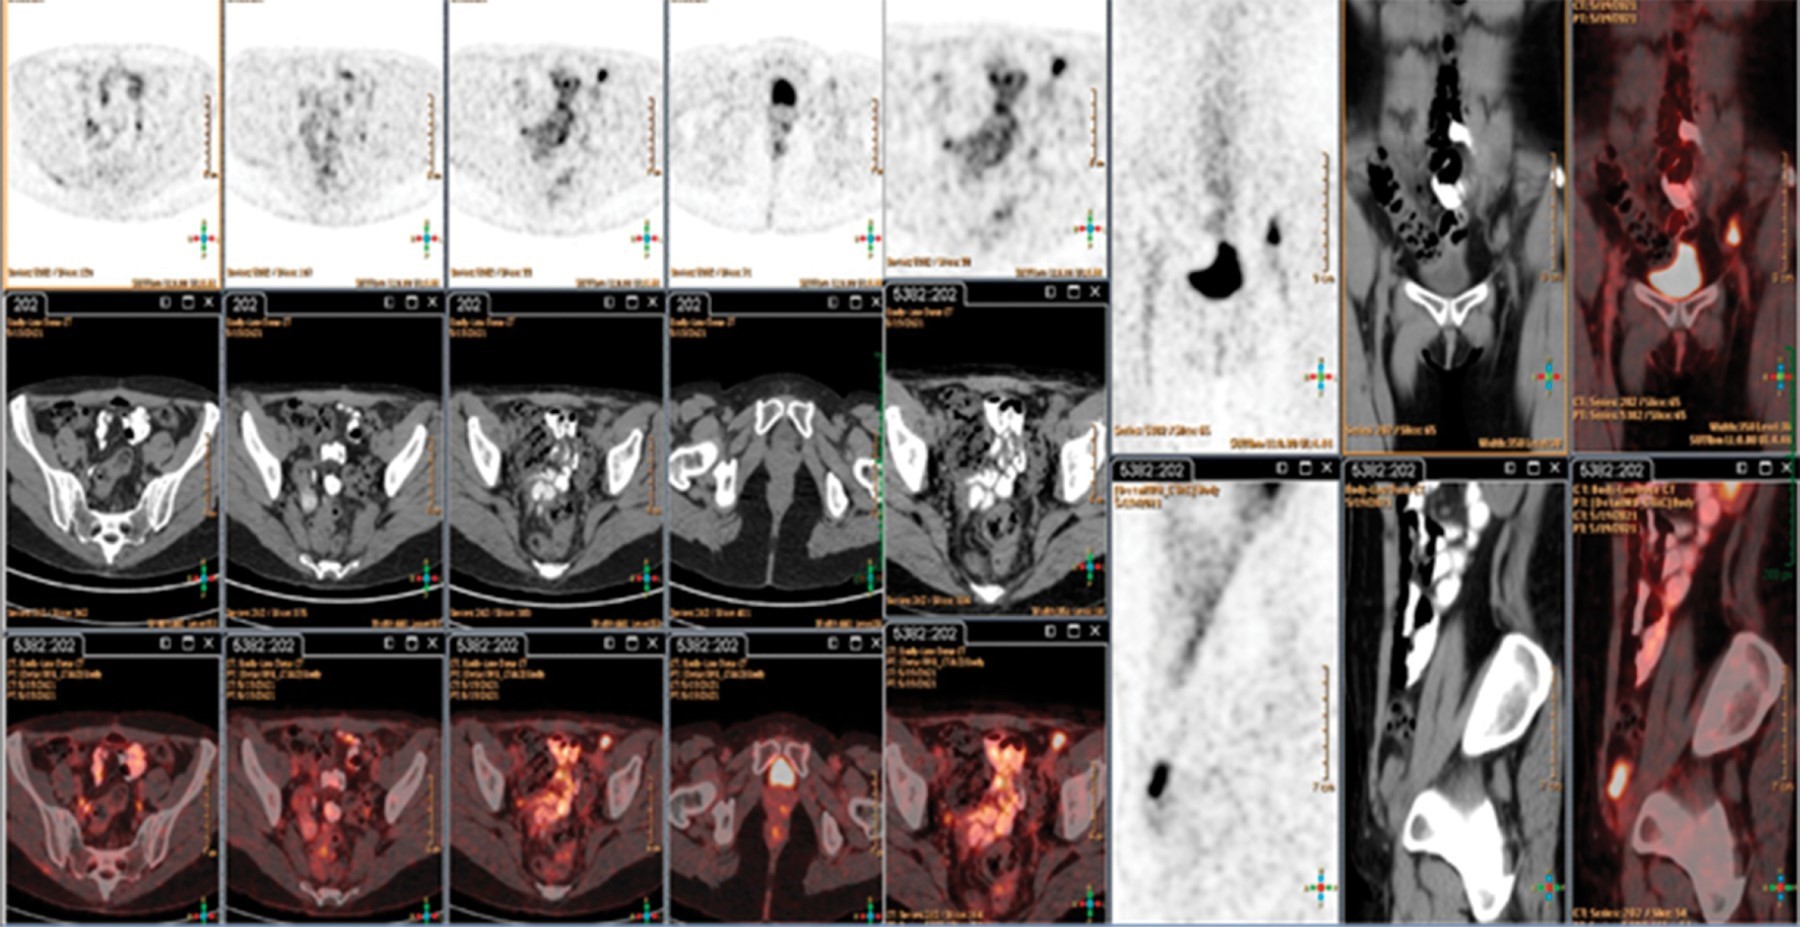

Femenino de 54 años con diagnóstico de cáncer de ovario estadio IIIC que había sido sometida a citorreducción quirúrgica y quimioterapia sin evidencia de recurrencia, se presenta en el servicio de urgencias con un síndrome cerebeloso subagudo. El estudio de imagen descarta alteraciones estructurales, punción lumbar con pleocitosis linfocitaria, hiperproteinorraquia y anti-Yo positivo, con actividad tumoral inguinal confirmada por PET-CT.

Se trata de una paciente en la quinta década de la vida con diagnóstico de cáncer de ovario en estadio IIIC sometida a quimioterapia y citorreducción quirúrgica. Dado que la mayoría de los síndromes paraneoplásicos debutan como parte de la presentación inicial de la enfermedad, este caso es peculiar. Presenta un síndrome paraneoplásico agregado a una adenopatía inguinal con actividad documentada por tomografía por emisión de positrones, lo cual es una presentación atípica de un síndrome poco documentado.

Inicia seis días previos a su ingreso con diplopía bilateral, mareo e inestabilidad postural. A su ingreso se presenta alerta con nistagmus multidireccional no fatigable, trofismo y fuerza muscular normal, destaca arreflexia y marcha atáxica con signo de Romberg presente. Se realiza resonancia magnética que se reporta normal con subsecuente punción lumbar, no se reportan hallazgos relevantes en citología y citoquímica, la paciente presenta anticuerpos anti-Yo positivos (≥ 1:10), por lo que se establece síndrome paraneoplásico con recurrencia de la enfermedad confirmada por tomografía por emisión de positrones a nivel ganglionar inguinal izquierdo (Figuras 1 y 2).

Figura 1